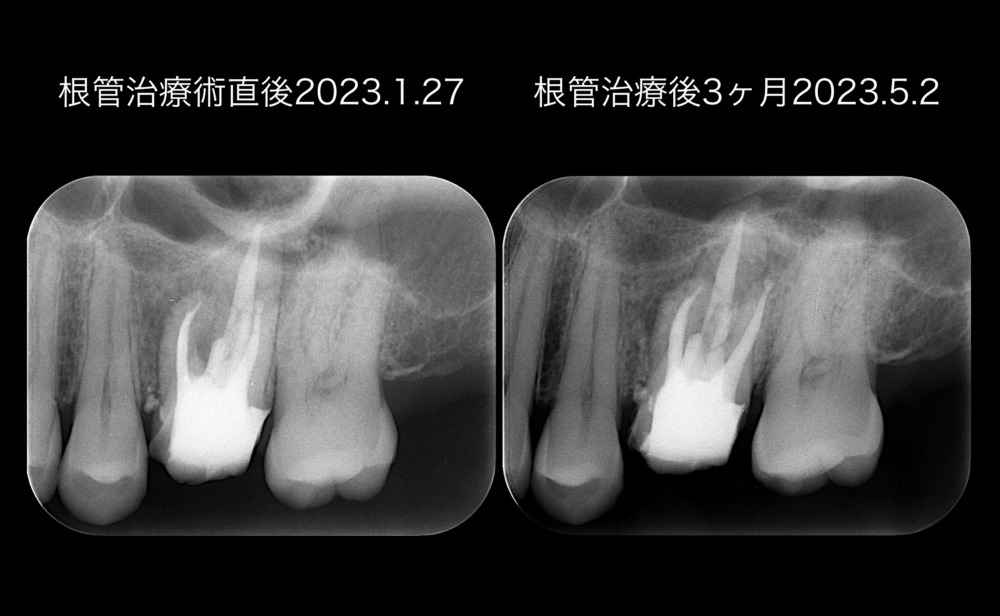

術後3ヶ月経過時点でのデンタルを術直後と比較しても、根尖部透過像の境界が不明瞭なので、CTを撮影しました。